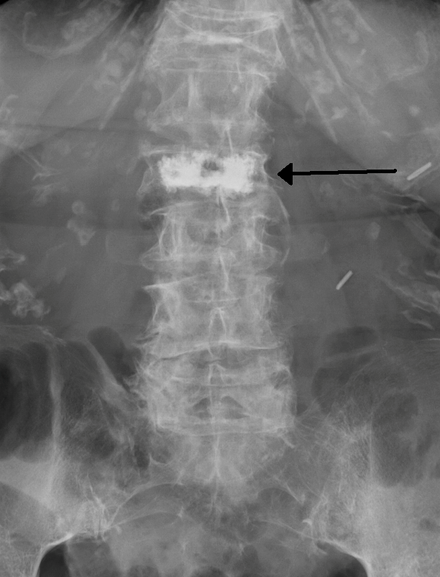

Bone cement in a vertebra (black arrow) as seen on a plain X-ray